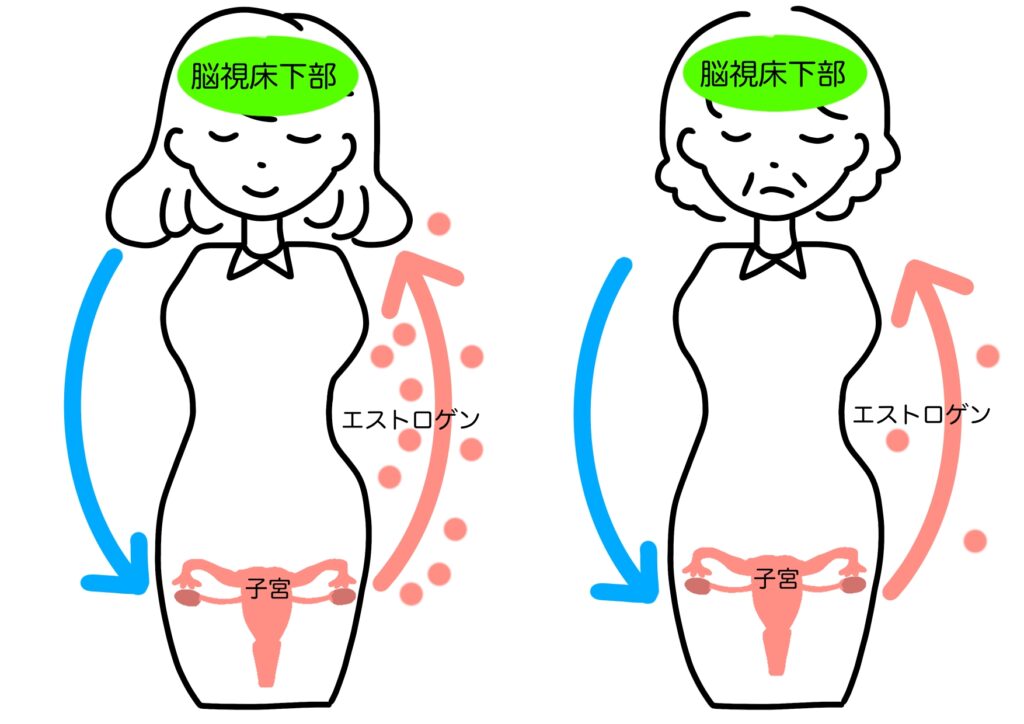

更年期の不調をひと言でいうと、

「体内の司令塔と現場の連携が乱れ、

脳も自律神経も大慌てしている状態」です。

体の中では本来、

• 脳が「女性ホルモンを出してね」と指示を出す

• 卵巣が「了解」と応える

という流れがスムーズに行われています。

ところが更年期になると、卵巣の働きがゆらぎ、

エストロゲン分泌が不安定になります。すると脳は

「え、出ないの?もっと出して!」と指令を強め、

その影響で自律神経のバランスまで乱れやすくなります。